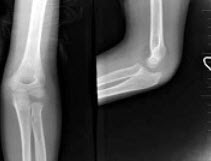

E.以上都不是

160、单项选择题

8岁,男孩,外伤后感左肘关节肿痛,左肘关节正侧位摄片如图,下列哪项描述错误()

A.“八”字征

B.“X”线白线不连续

C.软组织肿胀

D.左肱骨小头骺线增宽

E.以上均正确

201、单项选择题

女,2岁,肘部外伤,如图所示,最佳的诊断为()

A.肱骨髁上骨折

B.肱骨髁上骨折并肘关节脱位

C.内上髁骨骺损伤

D.内上髁骨骺损伤并肘关节脱位

E.全骺分离

235、单项选择题

女,6岁,外伤后左肘部肿痛,活动受限,外髁局部压痛,X线摄片如图,最可能的诊断是()

A.左肱骨小头骨骺损伤

B.左肱骨髁上骨折

C.左肱骨外上髁骨骺损伤

D.左肱骨内髁骨骺损伤

E.左肱骨外髁骨骺损伤